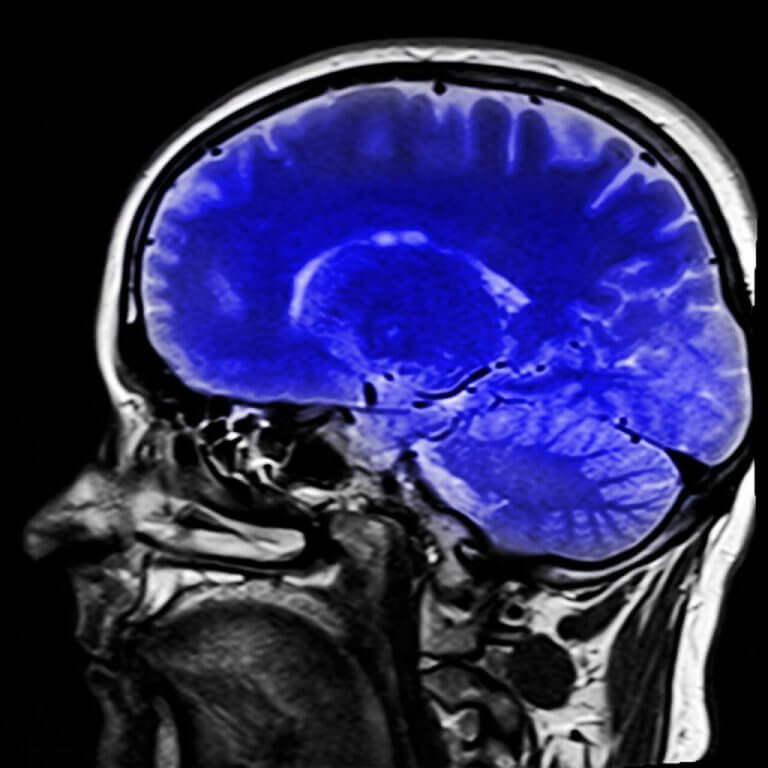

Bu sendroumun teşhis edilmesinde doktorlara yardımcı olan nörolojik testler bulunuyor. Emar taraması ne tarz bir felç olduğunu gösterebilir ve bu ne olduğunun belirlenmesi için yardımcı olabilir.

Pozitron yayınlayıcı tomografi (PET) de elektroansefalogram (EEG) da doktorlara hastanın beyinsel aktivitesi ile ilgili bilgi verebilir. PET taraması beyin metabolizmasının normal olup olmadığı gösterebilir. Ve eğer normalse, bu tüm beyin fonksiyonlarının çalıştığını ve kilitli kalma sendromundaki gibi hastanın bilincinin açık olduğunu gösterir.